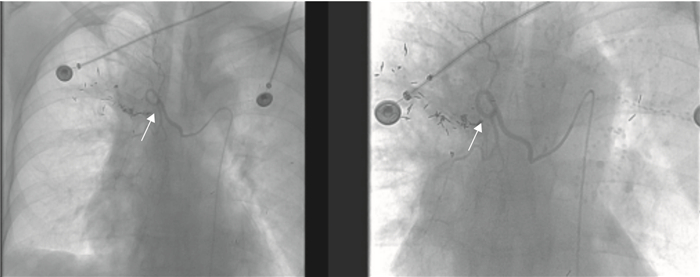

3.動脈灌注術:對患者行常規準備后,患者取仰臥位,為避免或減少并發癥及不良反應出現,術前先給予患者地塞米松10 mg靜脈注射,常規行雙側股動脈區域消毒,鋪巾,2%利多卡因右側或左側股動脈周圍局麻。應用Seldinger技術穿刺右側或左側股動脈成功后,置入5F動脈鞘,經導管鞘送入Cook公司生產的5F蛇管,造影確認腫瘤的供血動脈(圖 2),腺癌患者經供血動脈注入培美曲塞500 mg/m2和順鉑75 mg/m2,鱗癌患者注入表柔比星30~40 mg和順鉑75 mg/m2,每3周灌注1次,灌注完畢后撤出導管及動脈鞘,壓迫10 min,局部加壓包扎,術中嚴密監測血壓、呼吸、脈搏、血氧飽和度等各項指標。

穿刺的腫瘤灶(空心箭);已經穿刺至靶點的穿刺針(白箭);已經完成植入的125I粒子(白箭頭)